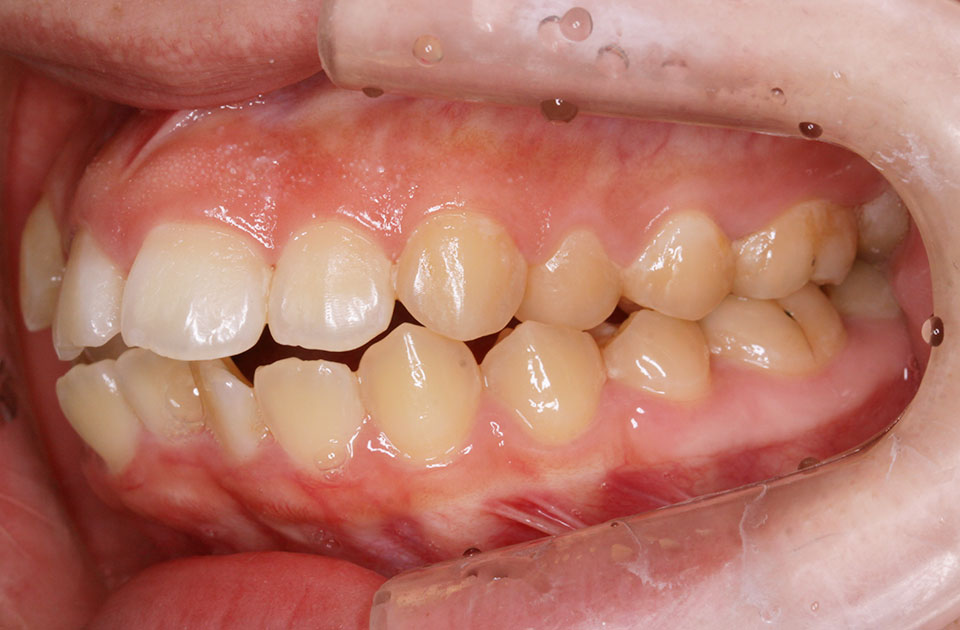

矯正前 右側

矯正前 左側